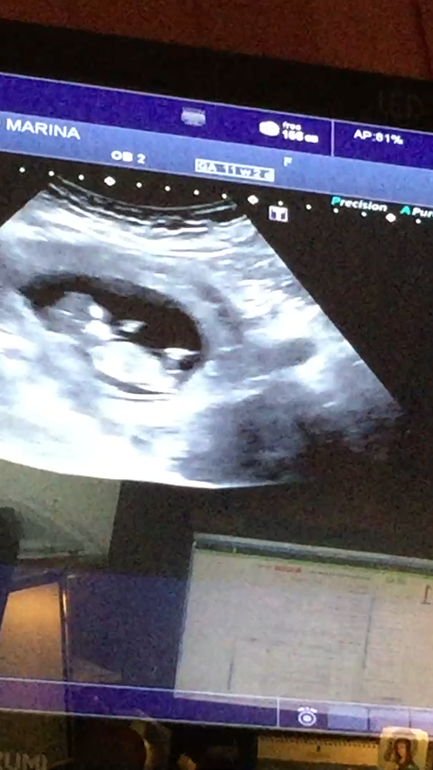

УЗИ в 25 роддоме. Рубеж 1 триместра.

У нас получилось! Я беременна!И так, прошли мы сегодня скрининг в 25 рд. Фотку конечно не сделали, бумаги у них нет! Как обычно, савок! Но я поснимала все на телефон и похоже у нас все же мальчик! Все показатели в норме, тттттт. Слава богу! Вес у меня уменьшился с 70550 до 70100. Вечером вообще не могу кушать. Ну и вот, что удалось сфоткать